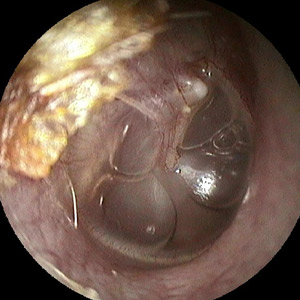

Serotympanon

Flüssigkeitsansammlungen im Mittelohr, einen Mittelohrerguss, z.B. bei einem Schnupfen, kann jeder Mensch zeitweise haben. Dieses Phänomen wird als Tubenkatarrh bezeichnet. Bleibt dieser Erguss im Mittelohr (Wasser im Ohr) bestehen oder tritt er immer wieder auf, so bezeichnet man dies als chronische Mittelohrenzündung. Hier spricht man von der chronisch serösen oder chronisch mukösen Form der Mittelohrentzündung. Diese tritt im Kinderalter häufiger auf als bei Erwachsenen.